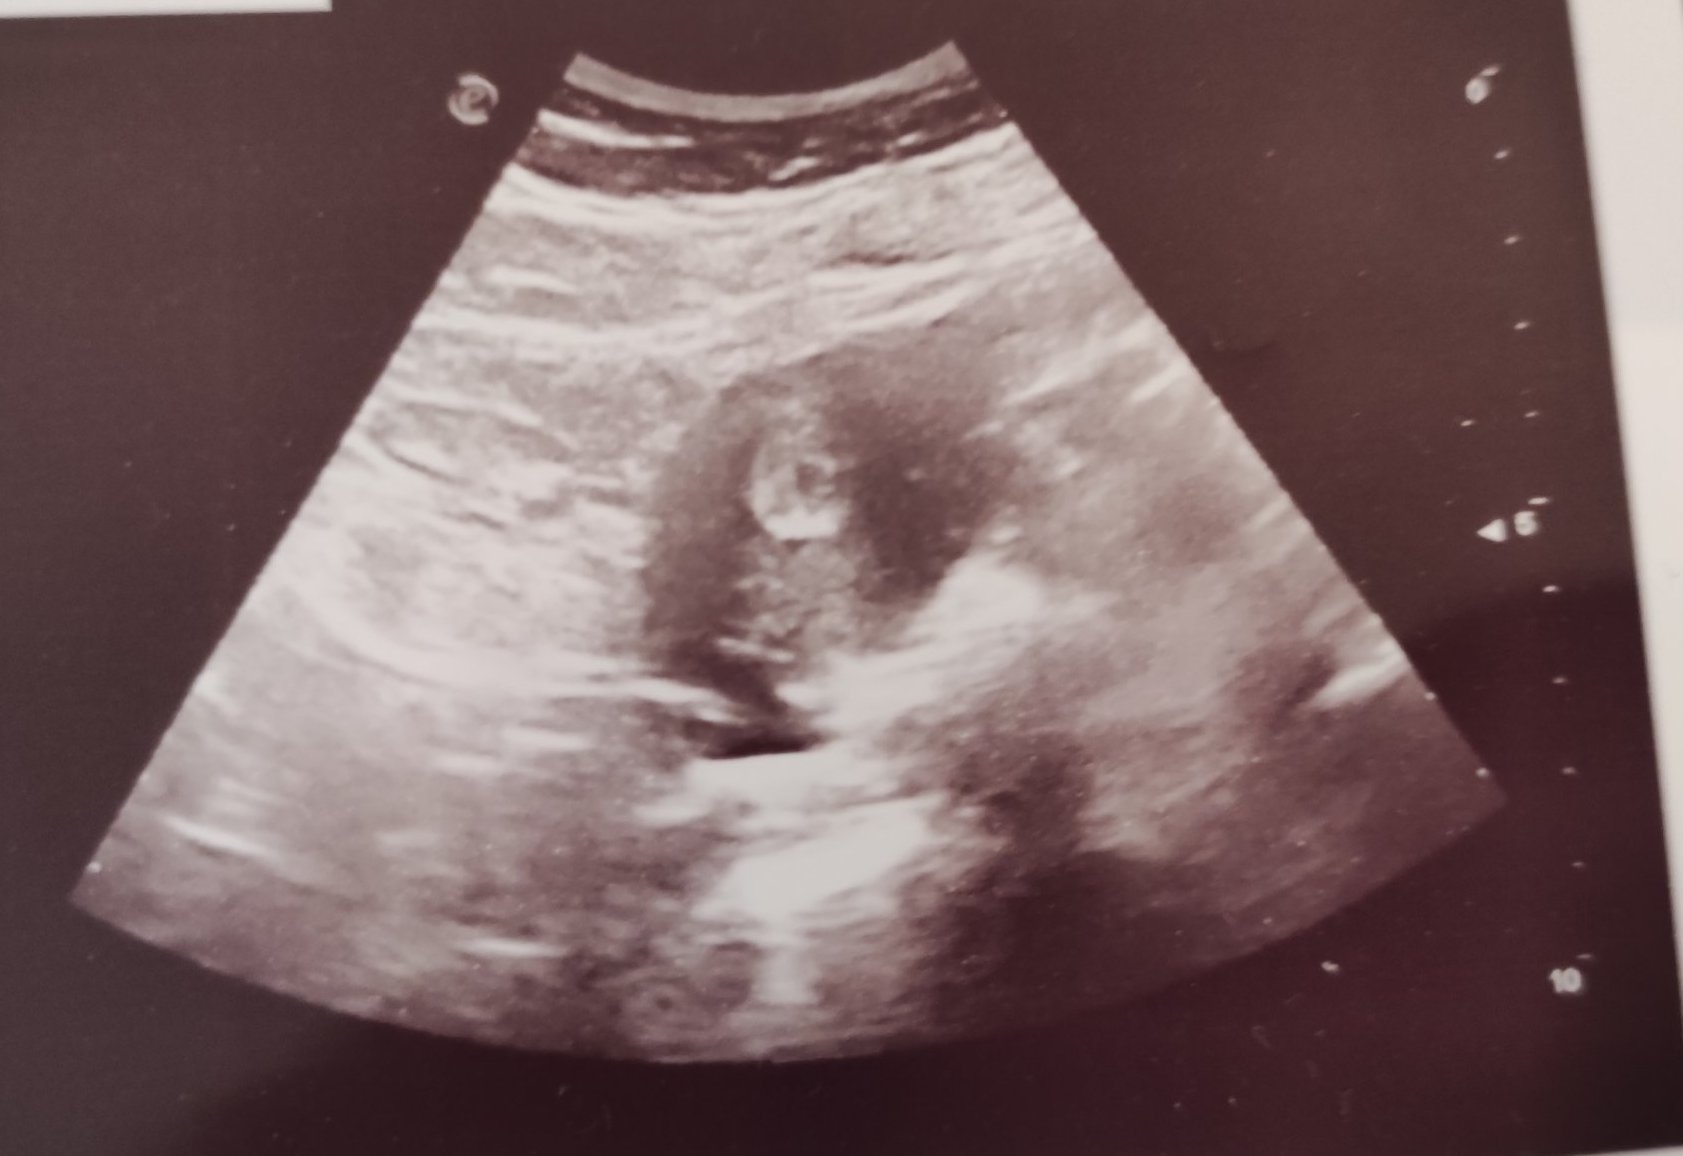

Какво представлява изображението от ехографията на 5-седмична и 2-дневна бременност?